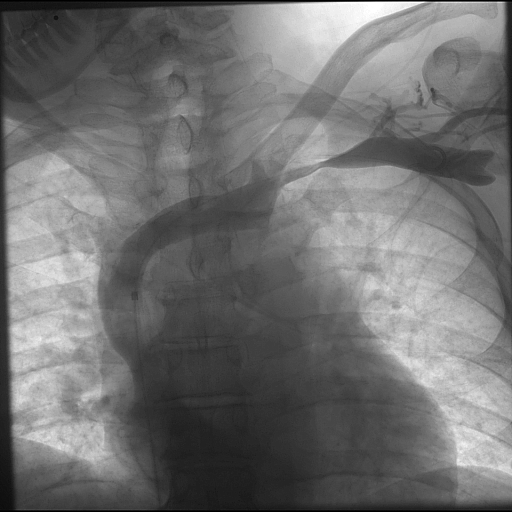

Venography is recommended in two instances. First, if the diagnosis is suspected, but proof was not obtained otherwise. For instance, when the duplex is inconclusive. The second use for venography, of course, is during a procedure. Venography often reveals venous collaterals, suggesting chronic sub-total compressions have been present. Furthermore, venography can be performed when the hand is in the neutral position or abducted. If extrinsic compression is visible, that suggests Paget Schroetter. Surprisingly CT and MR are not well suited imaging modalities for diagnosing Paget Schroetter, despite their obvious capabilities in diagnosing clot per se.